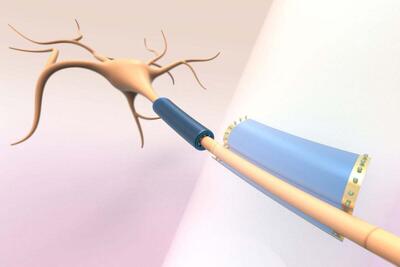

کشف شگفتانگیز؛ حافظه فقط مختص سلولهای مغز نیست

سلولهای کلیه شبیه به بافتهای عصبی نورونها یادگیری دارند.